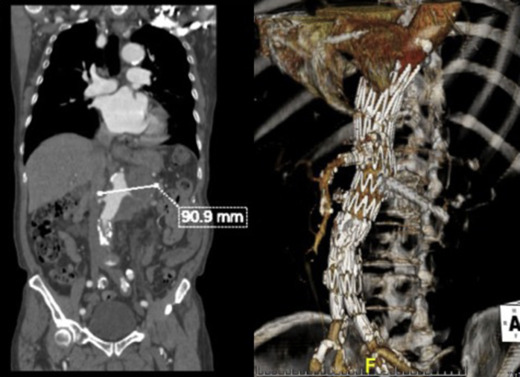

The ruptured group presented survival rates of 53.5%, 50.5%, 47.5%, 42.3%, 38.0%, 21.9%, and 12.5% at 1 year, 2 years, 3 years, 4 years, 5 years, 10 years, and 15 years, respectively; while the nonruptured group had survival rates of 91.5%, 88.0%, 83.7%, 78.3%, 73.0%, 43.0%, and 25.3% (log rank p < 0.001; Fig. 2). For those who died 30 days after their operation, only six patients died from aneurysm related causes, giving a late aneurysm-related mortality of 1.8% (Table 5). There were a total of three (0.9%) patients who underwent late re-interventions due to graft related events. The first patient underwent open repair in 1994 at the age of 66 years. The 4.4 cm infrarenal aortic aneurysm and 5.7 cm left iliac aneurysm were replaced with aorto-bi-iliac knitted Dacron graft. He presented with recurrent gastrointestinal bleeding of unknown origin 6 years later. Upper endoscopy and colonoscopy failed to localize the bleeding source. Laparotomy and enteroscopy showed suspicious bleeding from the proximal jejunum and possible graft-to-jejunum fistula. Bleeding was settled with aorto-uni-iliac endovascular stenting and cross femoral bypass. The patient is still alive to date (Fig. 3). The second patient underwent open repair with aorto-bi-femoral woven Dacron graft in 1993 at the age of 72 years. Seven years later, he was incidentally found to have a pulsatile mass at the epigastrium with a CT scan showing an infrarenal 8 cm proximal anastomosis pseudoaneurysm. Treatment was standard endovascular repair (Fig. 4). The last patient had open repair surgery with aorto-bi-iliac woven Dacron graft in 1993 at the age of 76 years. He complained of epigastric pain 20 years later with a CT scan showing a 9 cm proximal perivisceral pseudoaneurysm, which was settled with endovascular stenting with fenestration to all four visceral vessels (Fig. 5; Table 6). In addition, 17 (5.0%) patients developed thoracic or iliac aneurysms in later life. They were treated with open or endovascular repair (Table 7).

Late intervention, Patient 3.

Fig. 5.